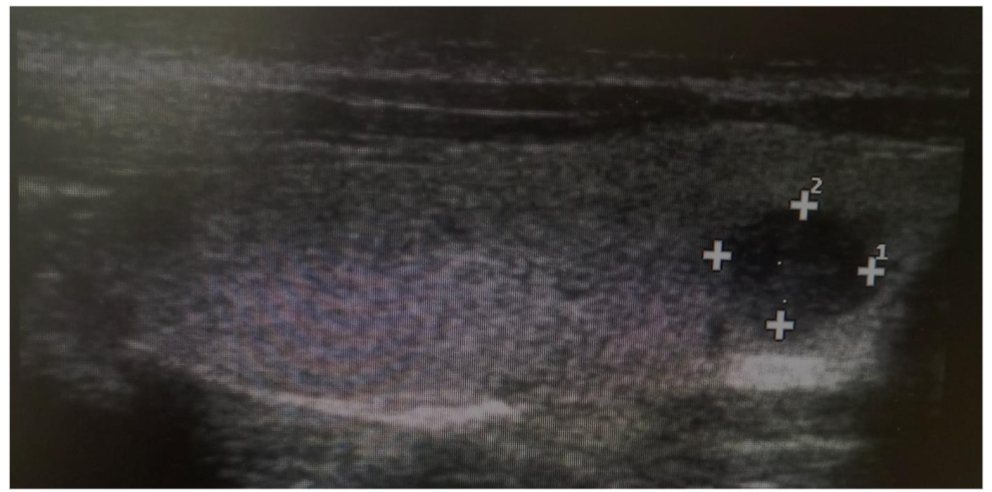

Figure 2. A Sample of Sagittal View of Thyroid Sonogram for A 22 years, Female Participant Demonstrating a Solitary Solid Nodule.